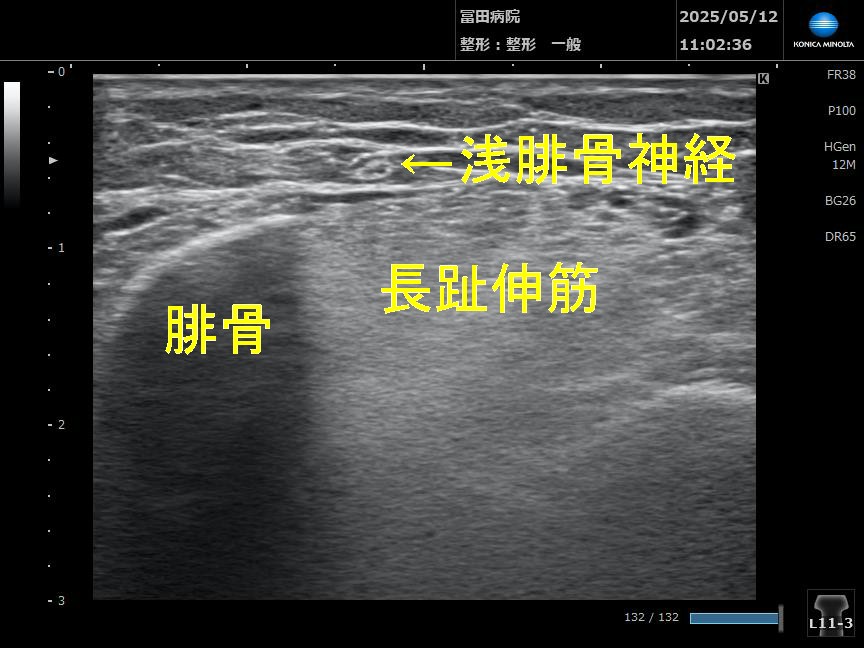

エコー画像で確認してみます

次にエコープローブを上下に動かし神経が筋膜上に出てくるところを確認します

この部位には長趾伸筋筋膜下から表層に出てくる場所でこの部位にて神経狭窄や神経癒着が起きやすいようですね。